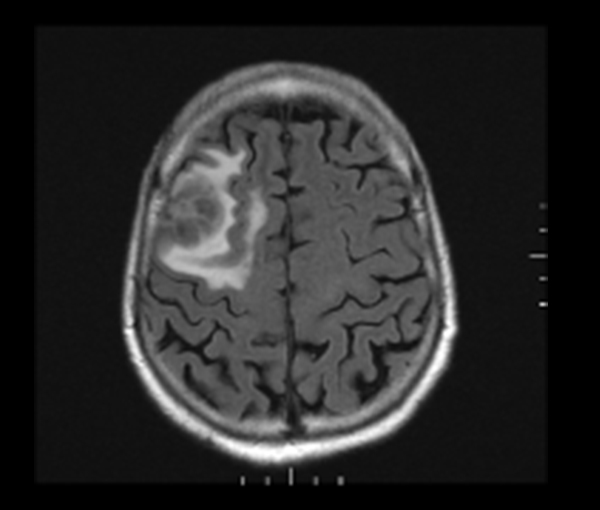

Cerveau translation in French English Reverso dictionary, see also 'cerveau électronique',lavage de cerveau',rhume de cerveau',cerceau', examples, definition, conjugation. Scanner translation in French English Reverso dictionary, see also 'scander',savonner',scandale',scansion', examples, definition, conjugation. Le terme « cancer du cerveau » désigne des tumeurs cérébrales variées Différents cancers du cerveau Ces tumeurs peuvent se développer dans différents endroits, notamment le cervelet.

Tumeurs Du Cerveau Definition Symptomes Traitements Sciences Et Avenir